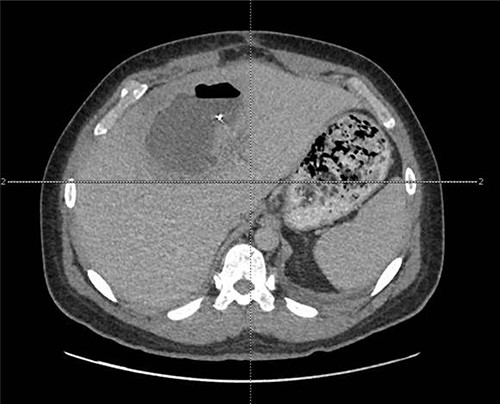

The patient presented after ingestion of an open paperclip and insertion of a sewing needle into his ventral hernia ~4 months prior. He presented with fever, tachycardia and abdominal pain, but a benign abdominal exam, noting only mild tenderness over his large, reducible ventral hernia. A computed tomography (CT) of the abdomen and pelvis showed a 10-cm metallic foreign body extending from the mid transverse colon to the left hepatic lobe with an intrahepatic abscess measuring 9.1 x 7.3 cm (Figs 1–3). In addition, there were two other metallic foreign bodies: one extraluminal in the left upper quadrant, which was stable from prior imaging, and a subcutaneous foreign body above the hernia contents. Blood cultures grew streptococcus intermedius and he was started on broad spectrum antibiotics (piperacillin–tazobactam). The case was discussed with Interventional Radiology (IR) and deemed reasonable for attempt at percutaneous abscess drainage and trans-hepatic foreign body retrieval.

CT view of metallic foreign body within the liver abscess cavity.